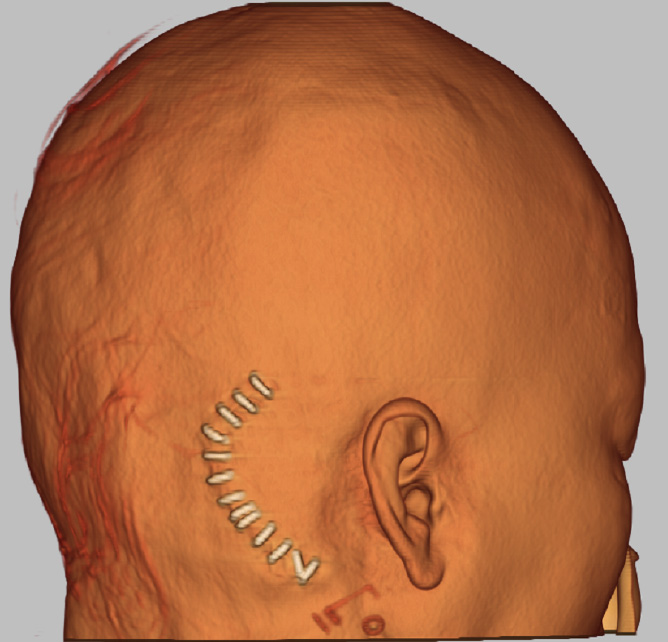

創部画像

なるべく傷が目立たないような工夫をしています。

二重線に沿った傷

手術後1週間程度でほぼ目立ちません